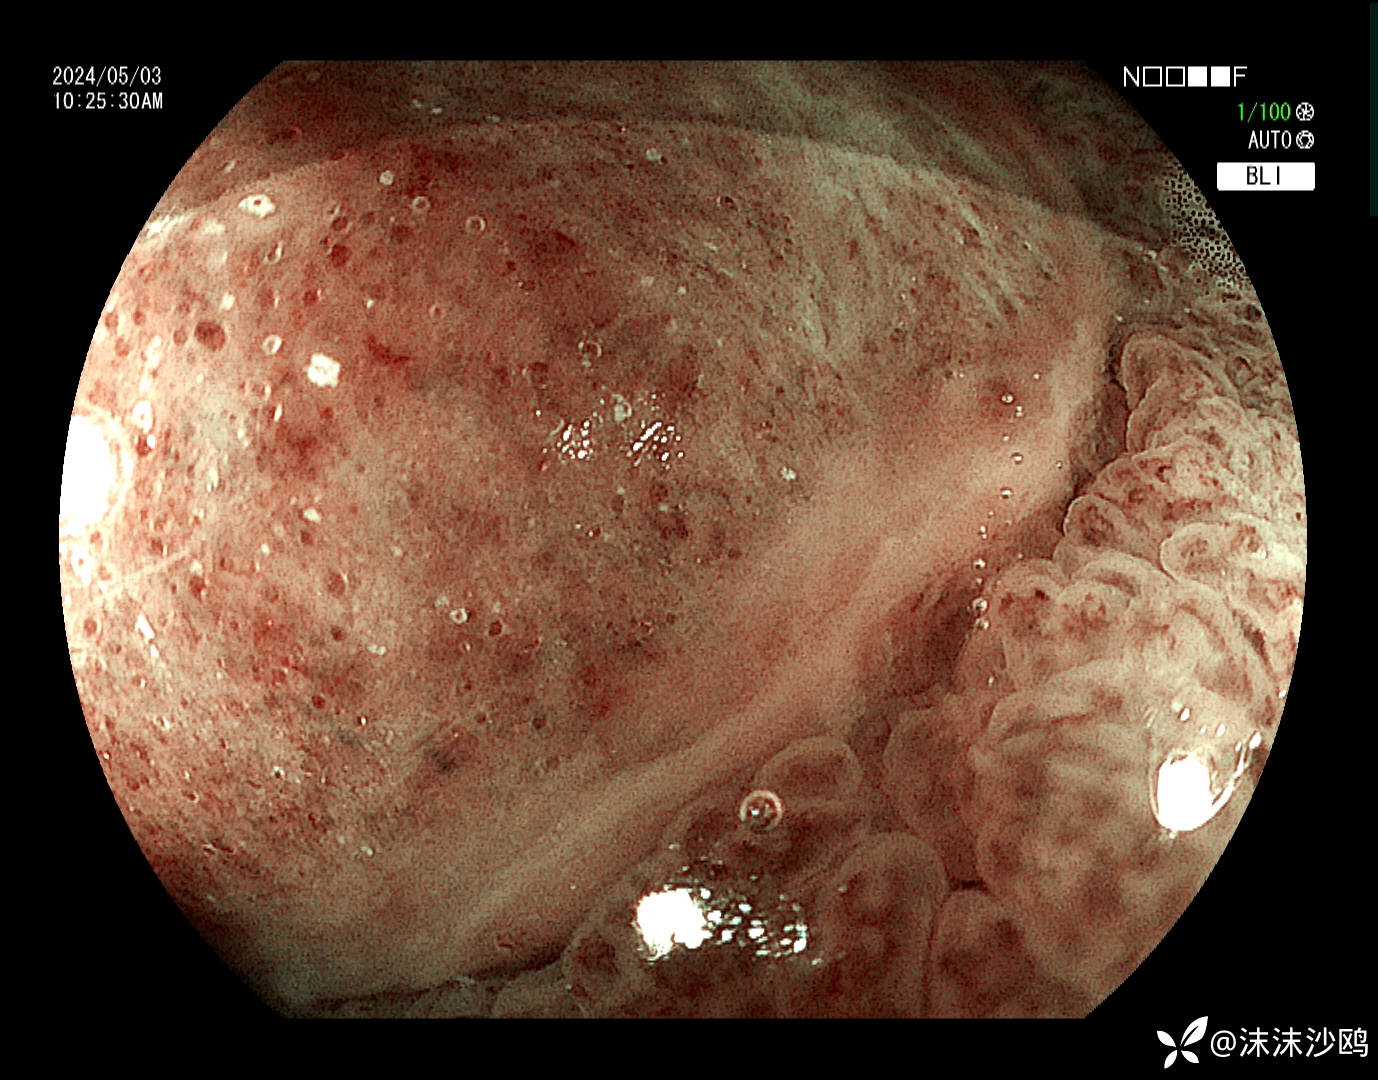

窦体交界近胃角前壁见一较大带蒂隆起性病灶,头端大小直径约2.5cm可见分叶结构,中央隆起跟边缘隆起的表面结构明显不同且有分界,沿分界线走向可见溃疡覆白苔。大致看上去就像一颗水煮蛋剥掉一部分蛋清露出蛋黄的感觉。

蒂部直径约1cm,凹陷见连续性溃疡,局部可见类似红色再生上皮?

表面没有明显的腺管结构,覆较多黏液冲洗不掉

BLI

边缘的表面结构呈脑回状